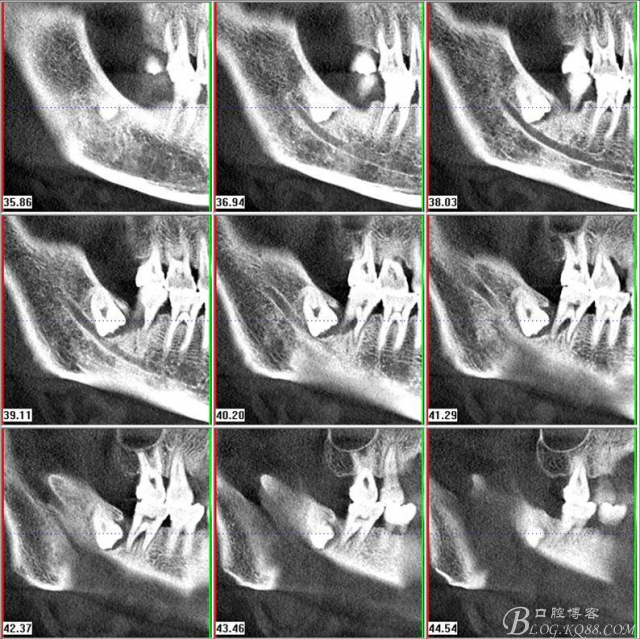

二、術前CBCT影像:

圖3.通過矢狀面和冠狀面來判斷48與下頜管及47的關系

圖6.測量48頰、舌側骨板厚度。

圖7.測量牙冠近遠中徑的大小及遠中骨板的厚度